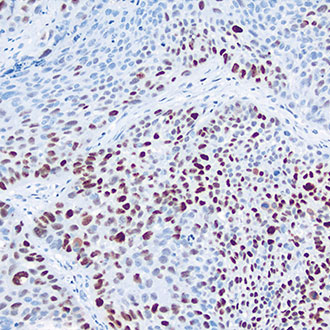

p53

p53 -